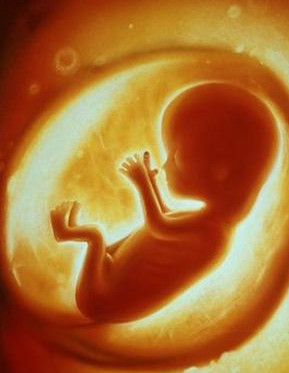

是指怀孕时子宫羊膜腔内的液体。在整个怀孕过程中,它是维持胎儿生命所不可缺少的重要成分。在胎儿的不同发育阶段,羊水的来源也各不相同。在妊娠第一个三月期,羊水主要来自胚胎的血浆成分;之后,随着胚胎的器官开始成熟发育,其他诸如胎儿的尿液、呼吸系统、胃肠道、脐带、胎盘表面等等,也都成为了羊水的来源。

羊水的颜色随孕周增加而改变。足月以前,羊水是无色、澄清的液体;足月时因有胎脂,胎儿皮肤脱落细胞、毳毛、毛发等小片物混悬其中,羊水则呈轻度乳白色并混有白色的絮状物。